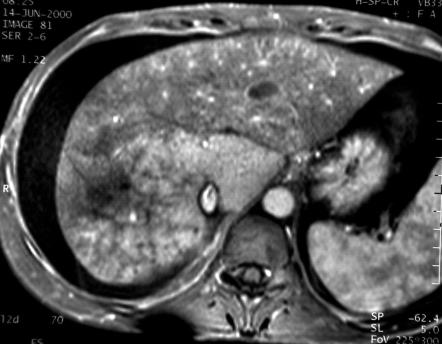

En pondération T2 les zones comprises dans la thrombose sont en

hypersignal.

L'étendue

de cette thrombose et la gravité des signes cliniques sont de mauvais

pronostiques. La patiente a été proposée pour une

greffe hépatique dans les semaines qui ont suivi.